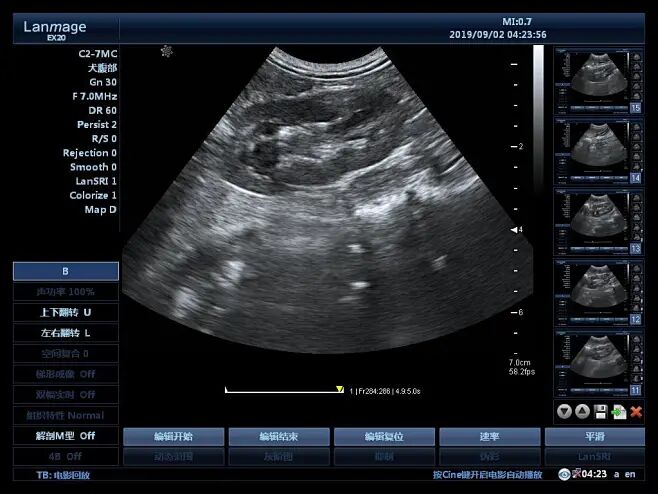

检查方法:借助超声设备测量胎儿的颈后透明层厚度,要求胎儿处于正中矢状位。

检查方法:在B超的引导下,用穿刺针穿过孕妇的腹壁和子宫壁,抽取少量羊水,然后对羊水内的胎儿细胞进行染色体核型分析等检查。